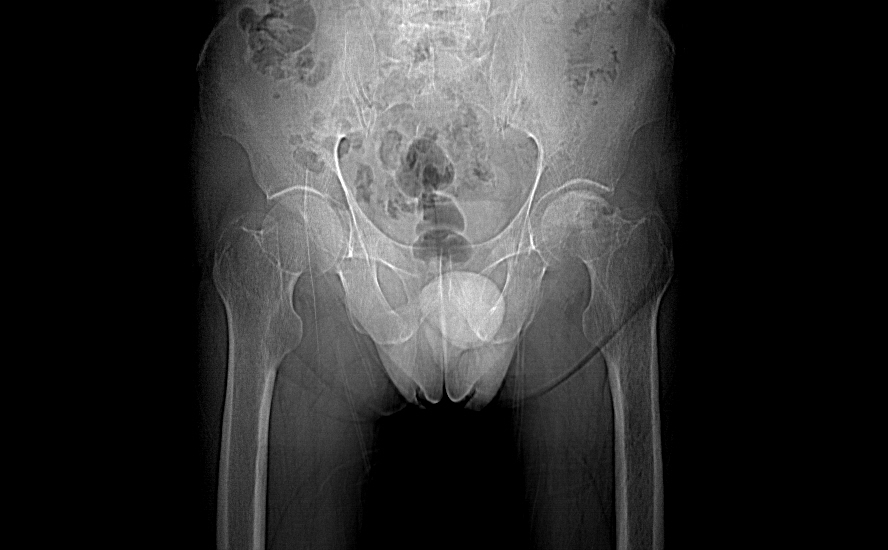

标题: CT11650:左髋病变,请会诊.

左髋疼痛不适近半年,局部无红肿热.无明确外伤病史.黄酒每天二餐.

考虑左侧股骨头缺血性坏死.(常期饮酒引起代谢障碍?)

左侧股骨头缺血性坏死;很典型。

“局部无红肿热.无明确外伤病史.黄酒每天二餐”。考虑左侧股骨头缺血性坏死。